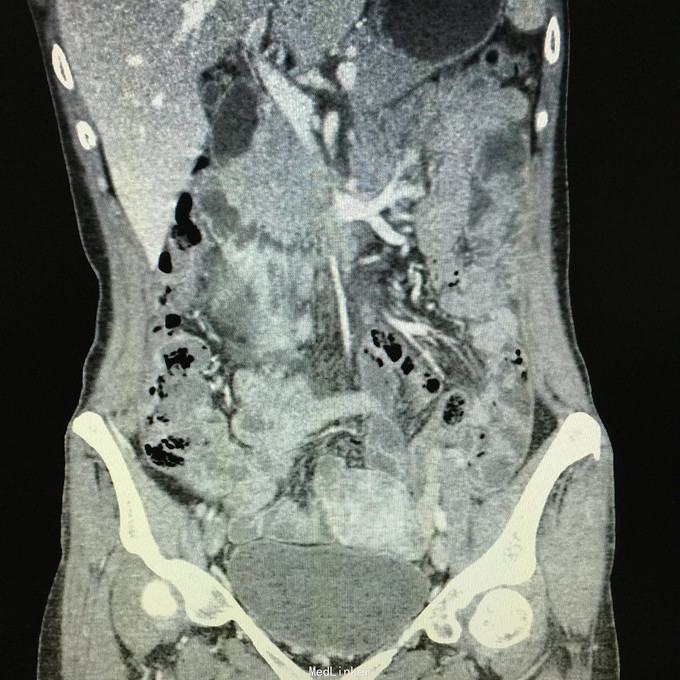

查体无特殊。 辅助检查:中下腹CT平扫+增强+CTU+CTA示:1.右输尿管中上段病变,考虑恶性病变,周围多发淋巴结转移,髂总动脉及髂外动脉起始部、髂内动脉中上段受侵闭塞,右侧腰大肌可疑受侵;建议输尿管镜检查;右肾重度积水,右肾功能明显受损。2.CTA示:右肾动脉纤细,肝右动脉起源于肠系膜上动脉。3.子宫体密度不均匀,建议MRI检查。中下腹MRI平扫+增强+MRU检查结果类似。

患者术后2月出现反复臀部疼痛,左侧为主,疼痛跑迷宫为隐痛,于翻身及活动时加重,卧床休息可稍缓解,多于下午出现,伴有发热,最高达39℃,在当地医院予“氟康唑”及止痛治疗后稍有缓解,但仍反复发热。后疼痛加剧,并出现双下肢疼痛,以大腿外侧为主,无间歇性跛行,无小腿及双足麻木疼痛不适,行对症治疗后效果不佳,于2015-10-9再次返院,予消炎止痛、营养支持及营养神经等治疗。查CT及MRI均提示骶髂关节炎症及腹膜后巨大病变,右侧髂总动脉及髂内、外动脉上段、右侧腰大肌受累。2015-10-15 14:00患者出现右下肢剧烈疼痛、右下肢乏力和麻木,随后出现2次血便,每次量约100ml,暗红色,无腹胀、腹痛等不适,查血提示白细胞 28.17*10E9/L,中性粒绝对值 25.33*10E9/L,血红蛋白56g/L,予止血、输血、抗真菌、止痛等治疗。19:00再次出现右下肢剧烈疼痛伴右下腹痛,查体:BP 80-90/50-60mmHg,P 100-106次/分,R 23次/分,SpO2 100%。右下腹轻压痛,反跳痛阴性,右下肢蹲背伸及踝背伸肌力II-III级,立即行全腹CT检查,示右髂总动脉假性动脉瘤破裂,予加强输注浓缩红细胞及补液支持治疗。清介入科会诊,考虑脓肿和感染为介入血管腔内支架置入治疗的禁忌症,建议予血管外科行开放手术,予患者及家属沟通,并转外院血管外科进一步治疗。